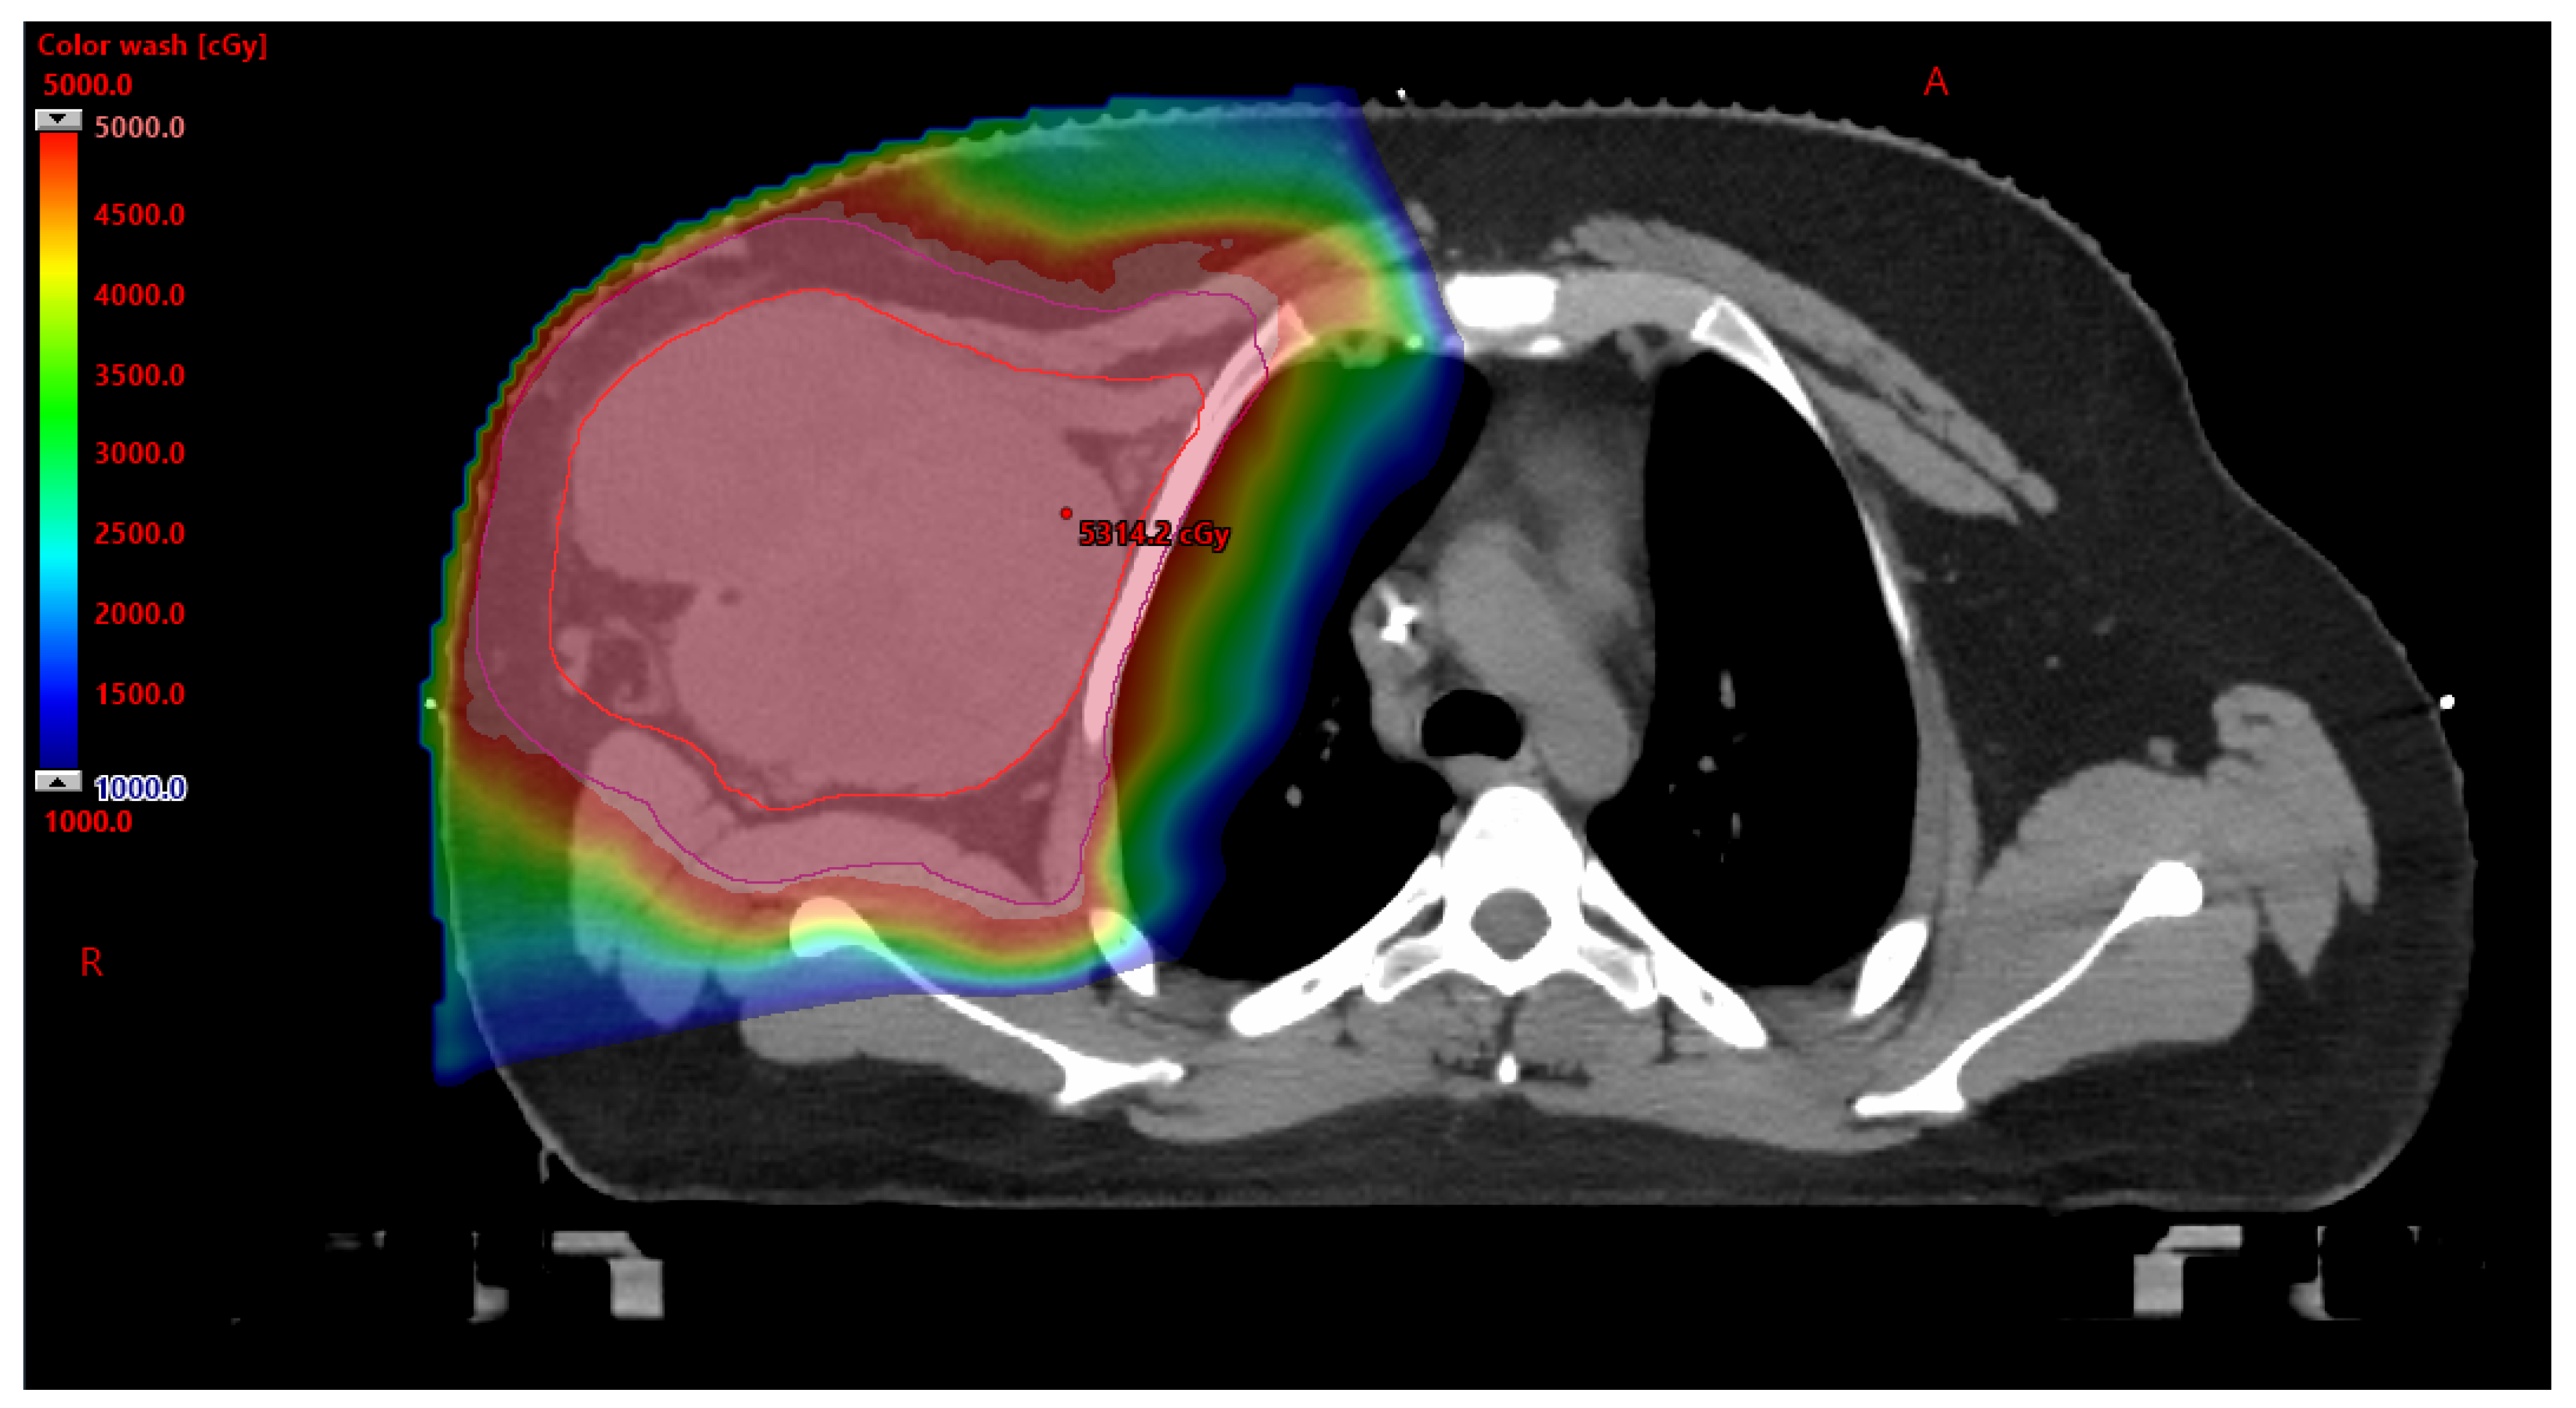

Figure 2. Additional view of the designed PBT treatment plan, which demonstrates PBT ability to avoid dosage to the right lung and heart. Mean heart dose was 0.15 Gy and mean right lung dose was 13.4 Gy. There was no radiation dose to the left lung. H: head R: right.

While the FDA approved PBT for the treatment of cancer in 1988, approval of PBT in the AYA population often proves to be difficult [13]. As part of an AYA sarcoma patient’s cancer care, radiation therapy is often utilized. With radiation therapy comes acute side effects, as well as long-term side effects. The AYA population is particularly susceptible to the development of radiation-therapy-related late toxicities—including organ dysfunction, hormone deficiency, fertility difficulties, cardiovascular disease, and secondary malignancies [14]. Due to young age and expected years of survivorship, limiting short-term and long-term side effects is essential for positive outcomes related to the control/cure of the disease and quality of life. Compared to photon-based radiation therapy, PBT can provide a clear dosimetric advantage by eliminating the exit dose and reducing the entry dose without compromising the tumoricidal dose, see Figure 1 and Figure 2 [14]. A clinical investigation was published in 2020 which explored treatment outcomes after PBT for Ewing sarcoma of the pelvis. The investigation explored overall survival and tumor control rates in thirty-five patients aged less than 21 with no metastatic pelvic Ewing sarcoma who received PBT and chemotherapy between 2010 and 2018. The findings highlighted the benefits of PBT. Patients with large tumors (≥8 cm) who underwent definitive PBT with a higher dose (>59.4 Gy RBE) remained free from tumor recurrence (n = 5) [15]. While this investigation was focused on patients under 21 years of age, it highlights the benefit of PBT providing local control and dose escalation without significant radiation toxicity for patients with Ewing sarcoma. Advantages of PBT for Ewing sarcoma of the cranium and skull base were explored through review of 25 patients ≤ 21 years old with non-metastatic Ewing sarcoma of the cranium and skull base that were treated between 2008 and 2019. Results found that the four-year local control, disease-free survival, and overall survival rates were 96%, 86%, and 92% [16], with none of the studied patients having developed a secondary malignancy. These findings call attention to the benefits of PBT in the treatment of AYA sarcoma patients and the opportunity to explore the role of PBT in the care of all AYA cancer patients. Despite the proven benefit of PBT in the treatment of AYA sarcoma patients, barriers to use have been identified.